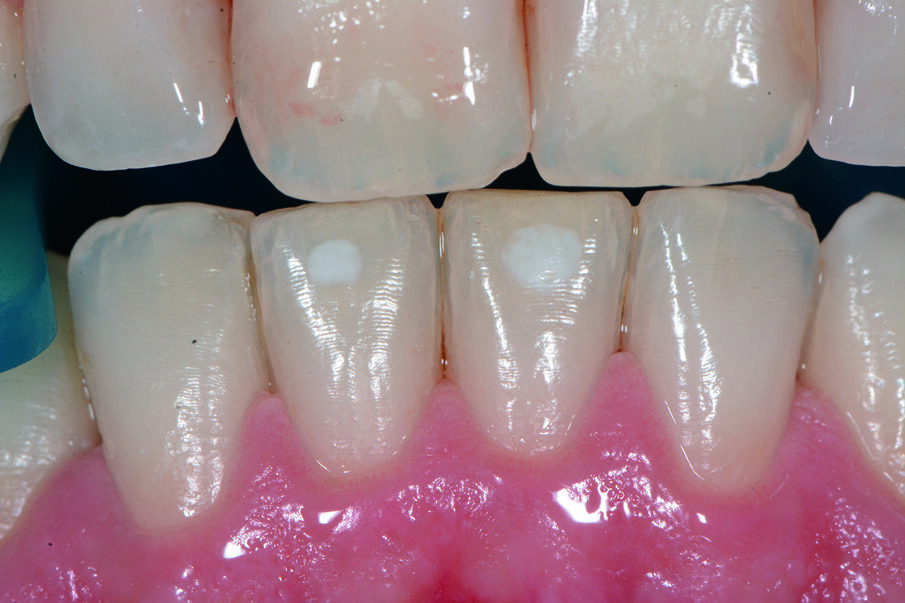

Durante l’esame obiettivo (Figg. 1a, 1b) rileviamo il danno iatrogeno da terapia ortodontica precedente alla visita e riscontriamo la presenza di processo carioso ICDAS 3 in zona 33 e in zona 47, white spots in zona 31 e 41. Durante l’esame obiettivo, l’ausilio della videocamera intraorale Sopro-Care (Acteon) permette, tramite filtri appositi, di evidenziare in modo rapido e accurato le zone di demineralizzazione e le aree infiammate e di mostrarle al paziente in real time, rendendolo attivamente partecipe e consapevole della situazione clinica (Figg. 2a-2f). I ricercatori del Baylor College of Dentistry hanno dimostrato che il 23,4% dei pazienti ha sviluppato almeno una white spot lesion durante il trattamento ortodontico.

Chiediamo al paziente se si fosse sottoposto a terapia ortodontica e il paziente riferisce di essersi sottoposto a terapia ortodontica in età adolescenziale per circa 2 anni e di non aver dato molta importanza alle lesioni presenti, poiché non aveva avuto grande sintomatologia riteneva che le white spots presenti non fossero un segno di demineralizzazione. Alla domanda della causa delle lesioni riferiamo che un inefficace controllo di placca domiciliare e uno stile di vita alimentare cariogeno, alzava il rischio di demineralizzazione delle lesioni che probabilmente erano state provocate dall’apposizione delle bande ortodontiche con materiale non di ultima generazione come i cementi vetroionomerici in grado di liberare fluoro. Inoltre riferiamo che durante la fase terminale del debonding, la topografia delle lesioni faceva presupporre l’uso poco attento di frese che avevano danneggiato lo smalto. Il paziente si mostra motivato e chiede una soluzione terapeutica che abbia come obiettivo la risoluzione funzionale ed estetica più veloce possibile. Viene condiviso con il paziente il piano terapeutico e proponiamo di iniziare con la terapia parodontale non chirurgica. Concordiamo con il paziente tempi, modalità di utilizzo e strumenti per migliorare il management degli stili di vita domiciliari, per il controllo chimico e meccanico del biofilm batterico (Nardi GM, Sabatini S, Guerra F, Tatullo M, Ottolenghi L. Tailored Brushing Method (TBM): an innovative simple protocol to improve the oral care. J Bio- med 2016; 1:26-31).